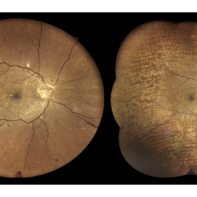

Central Retinal Vein Occlusion

Feb 25 2025 by Prithvi Chandrakanth

A 61-year-old woman with a history of hypertension noticed a sudden painless blurring of vision in her left eye. Over the next few days, the blurriness persisted, and she experienced a mild central scotoma. On examination, Fundoscopic evaluation revealed dilated, tortuous retinal veins, retinal hemorrhages, and macular oedema.

Photographer: DR.PRITHVI CHANDRAKANTH, DR.CHANDRAKANTH NETHRALAYA, KOZHIKODE

Imaging device: EIDON

Condition/keywords: CRVO, CRVO WITH MACULA EDEMA, flame shaped retinal hemorrhage